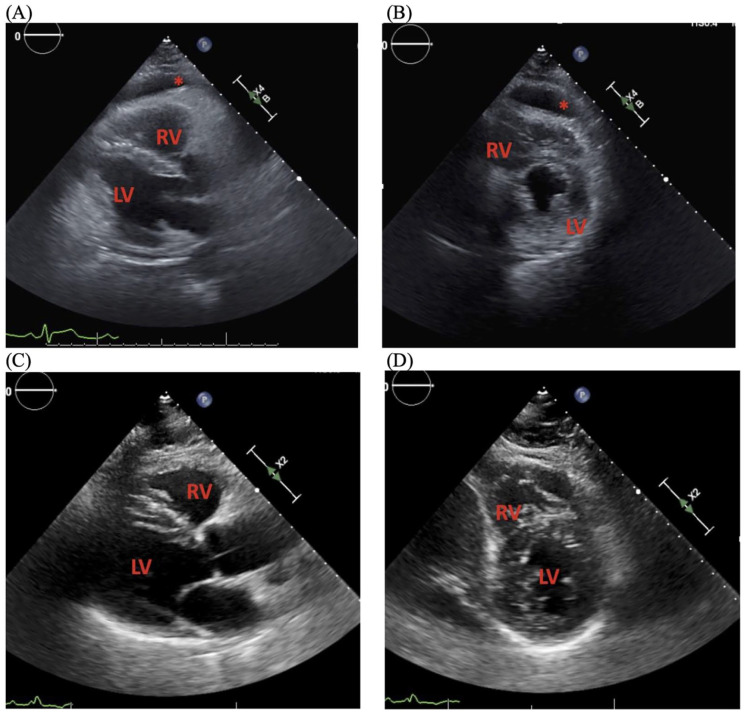

急性风湿热(ARF)是链球菌性咽炎的并发症,可伴有心脏、关节、皮肤和神经系统症状。心脏表现最常包括瓣膜功能障碍,但也可包括心肌炎或心包炎。尽管卫生保健方面的进步减少了链球菌性咽炎的流行,并随后减少了急性呼吸道感染,但仍可能发生个别病例和暴发。我们提出一例风湿性心包炎在一个60岁的白人男性谁最初提出的咽喉痛6天急诊科。最初的检查基本上是不起眼的,当时没有进行微生物检测。他被诊断为病毒性咽炎,在接受支持性治疗后出院。1周后复发胸膜性胸痛和呼吸困难。实验室检测显示炎症标志物、心脏酶标志物、抗溶血素O滴度和化脓性链球菌菌血症显著升高。进一步的评估显示心包炎,中度心包积液,无心包填塞,收缩功能降低,无瓣膜疾病。患者被诊断为风湿性心包炎。治疗方法包括心包引流、指南指导的药物治疗收缩期心力衰竭和心包炎,以及抗生素对ARF的一级治疗和二级预防。目前,患者的心脏功能已经恢复,他定期跟进他的医疗团队。虽然目前不太常见,但鼓励临床医生在出现咽部症状和随后的心脏表现,伴有或不伴有瓣膜功能障碍的患者的鉴别诊断中考虑链球菌性咽炎和ARF。一级和二级预防ARF对于维持该疾病的低发病率至关重要。

Acute rheumatic fever (ARF) is a complication of streptococcal pharyngitis that can present with cardiac, joint, skin, and neurological symptoms. Cardiac manifestations most often involve valvular dysfunction, but can also include myocarditis or pericarditis. Although advances in healthcare have reduced the prevalence of streptococcal pharyngitis, and subsequently ARF, individual cases and outbreaks can still occur. We present a case of rheumatic myopericarditis in a 60-year-old White male who initially presented to the emergency department with sore throat for 6 days. Initial workup was largely unremarkable, and no microbiological testing was performed at that time. He was diagnosed with presumed viral pharyngitis and discharged home with supportive care. He returned 1 week later with pleuritic mid-sternal chest pain and dyspnea. Laboratory tests were significant for elevated inflammatory markers, cardiac enzyme markers, anti-streptolysin O titers, and Streptococcus pyogenes bacteremia. Further evaluation revealed pericarditis, moderate pericardial effusion without tamponade, and reduced systolic function without valvular disease. The patient was diagnosed with rheumatic myopericarditis. Management included pericardial drainage, guideline-directed medical therapy for systolic heart failure and pericarditis, and primary treatment and secondary prevention of ARF with antibiotics. Currently, the patient's cardiac function has recovered, and he regularly follows up with his medical care team. Although less common in present times, clinicians are encouraged to consider streptococcal pharyngitis and ARF on the differential diagnosis for patients presenting with pharyngeal symptoms and subsequent cardiac manifestations, with or without valvular dysfunction. Primary and secondary prevention of ARF is paramount to maintaining the low incidence of this disease.